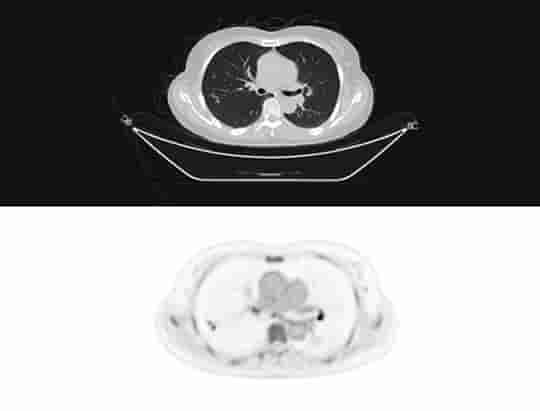

Przejrzystość obrazów uzyskiwanych z użyciem uMI Panorama wykracza poza pojedynczy parametr. System zapewnia wynoszącą 2,9 mm rozdzielczość PET wg NEMA oraz rozdzielczość czasową poniżej 200 ps, a 160-warstwowy tomograf komputerowy wykonuje pełny obrót w czasie 0,25 s z rozdzielczością przestrzenną 0,22 mm, gwarantując wysoką dokładność ilościową i wykrywalność małych zmian.

Wyposażony we wszelkie opcje 160-warstwowy diagnostyczny tomograf komputerowy o prędkości obrotu 0,25 sekundy i z wbudowanymi mechanizmami sztucznej inteligencji zapewnia wysoką jakość obrazu przy niskiej dawce promieniowania, dzięki czemu może być wykorzystywany jako samodzielny lub dodatkowy aparat do celów przeprowadzania zaawansowanych procedur radiologicznych.